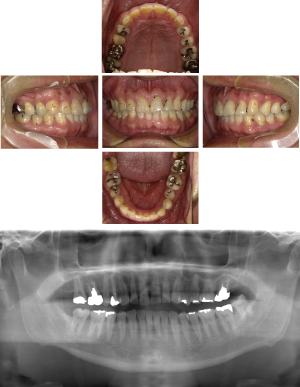

70代 女性 インプラント治療(GBR)

| 年代・性別 | 70代・女性 |

| 主訴 | 抜歯適応になってしまった所にインプラント治療希望。 |

| 部位 | 右上3・5(右上345のブリッジ)、右下6・7 左上4・6(左上456のブリッジ)、左下6・7 |

| 治療期間 | 約14ヶ月 |

| 費用 | ¥3,740,000(税込) |

| 副作用・リスク |